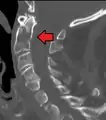

Fracture of dens

Repair of a dens fracture

Fractures of the dens, not to be confused with Hangman's fractures, are classified into three categories according to the Anderson Alonso system:

• Type I fracture - Extends through the tip of the dens. This type is usually stable.

• Type II fracture - Extends through the base of the dens. It is the most commonly encountered fracture for this region of the axis. This type is unstable and has a high rate of non-union.

• Type III fracture - Extends through the vertebral body of the axis. This type can be stable or unstable and may require surgery.